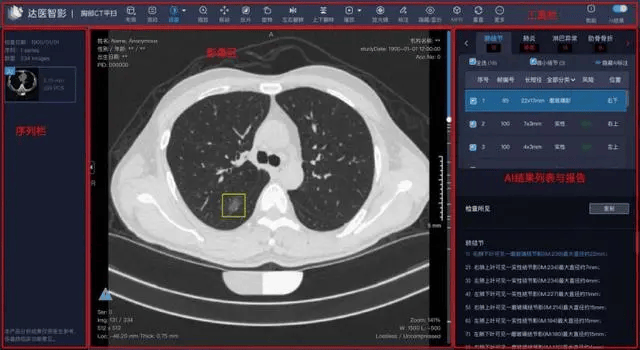

講真,雖然用AI來進行醫療影像檢查,早已在人類的預料之中,但這個技術真正成熟,卻是最近兩三年的事。

這也是為什麼,在阿里將這項成果的論文發表在《自然·醫學》上後,很多審稿人都不相信這類技術已經成熟到足以勝過人類了,以至於質疑聲不斷。直到後來,阿里在法蘭克福的節點上創建了一個可操作的demo,才消除了疑慮。

不過,或許令這些審稿人更難以相信的是,早在阿里推出PANDA之前,一個名叫coolwulf的中國“民間奇俠”,早在2018年就已經嘗試用50張1080Ti搭建了一個初級的 GPU 運算集,乳腺癌的檢測。

儘管歷經了這種種的侷限與困難,當coolwulf最終完成了 AI 檢測乳腺癌網站的搭建,並且向公眾免費開放後,腫瘤識別的準確率,仍然達到了 90%。

儘管當時coolwulf搭建的AI檢測平台,已經在乳腺癌檢測的準確率上十分出色,但本着與時俱進的精神,在算力大爆發的今天,coolwulf也在其最新的AI檢測項目——NeuralRad上,將GPU從1080Ti換成了4090。